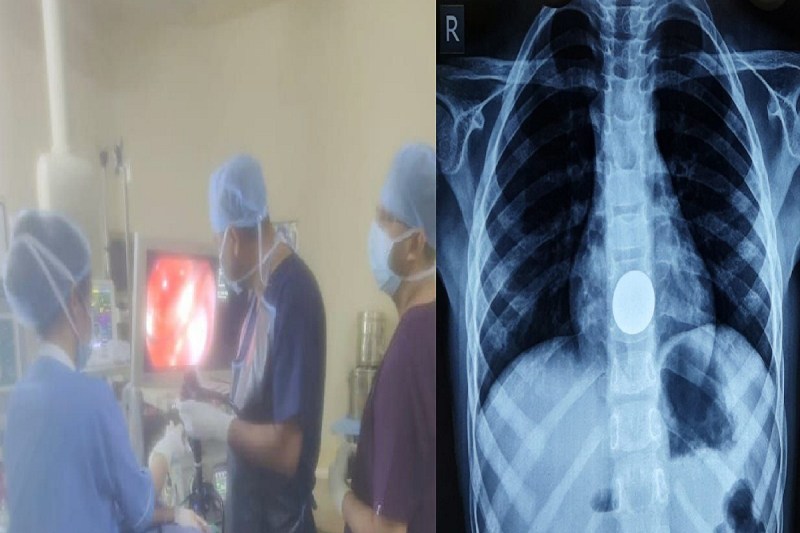

CG News: पीलू राम साहू/डीकेएस सुपर स्पेशलिटी अस्पताल में एक 8 साल के मासूम के पेट से सिक्का निकाला गया। खेल-खेल में मासूम ने दो रुपए का सिक्का निगल लिया था। सिक्का अन्न प्रणाली यानी ओसोफैगस में फंस गया था। इससे बच्चे को सीने में तेज दर्द होने लगा था। उसे कुछ निगलने में भी परेशानी हो रही थी।

पीडियाट्रिक सर्जरी विभाग के प्रोफेसर डॉ. जीवन पटेल की टीम ने एंडोस्कोपी से सिक्का को निकाल कर मासूम को नया जीवन दिया। अच्छी बात ये रही कि सिक्का निगलने के बाद मासूम के परिजन तत्काल डीकेएस पहुंचे। यहां एक्सरे व एंडोस्कोपी कर सिक्के की सही स्थिति के बारे में पता लगाया गया। फिर बिना चीर-फाड़ के सिक्का को बाहर निकाला गया। मासूम भी सुरक्षित है और उन्हें अस्पताल से जल्द ही डिस्चार्ज कर दिया जाएगा।

एक्सरे व एंडोस्कोपी से निगली गई चीज का सटीक अनुमान लगाया जा सकता है। अस्पताल अधीक्षक डॉ. क्षिप्रा शर्मा ने बताया कि डीकेएस में बच्चों की एंडोस्कोपी की पूरी सुविधा है। पहले भी फॉरेन बॉडी निकालकर बच्चों को ठीक किया गया है।